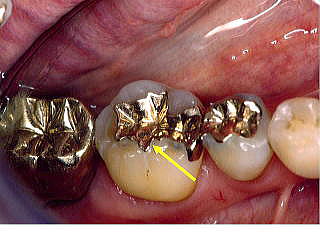

■症例1:酸食症 Acid Erosion

患者:54歳、女性。

当クリニックで装着したインレーが島状に浮き上がっている。(周囲のエナメル質の溶解)。6ヵ月間、就寝前に酸性水(通信販売)でうがいをしていた。使用した“強酸性水”のpH3.0以下。失ったEnamel質は戻らない